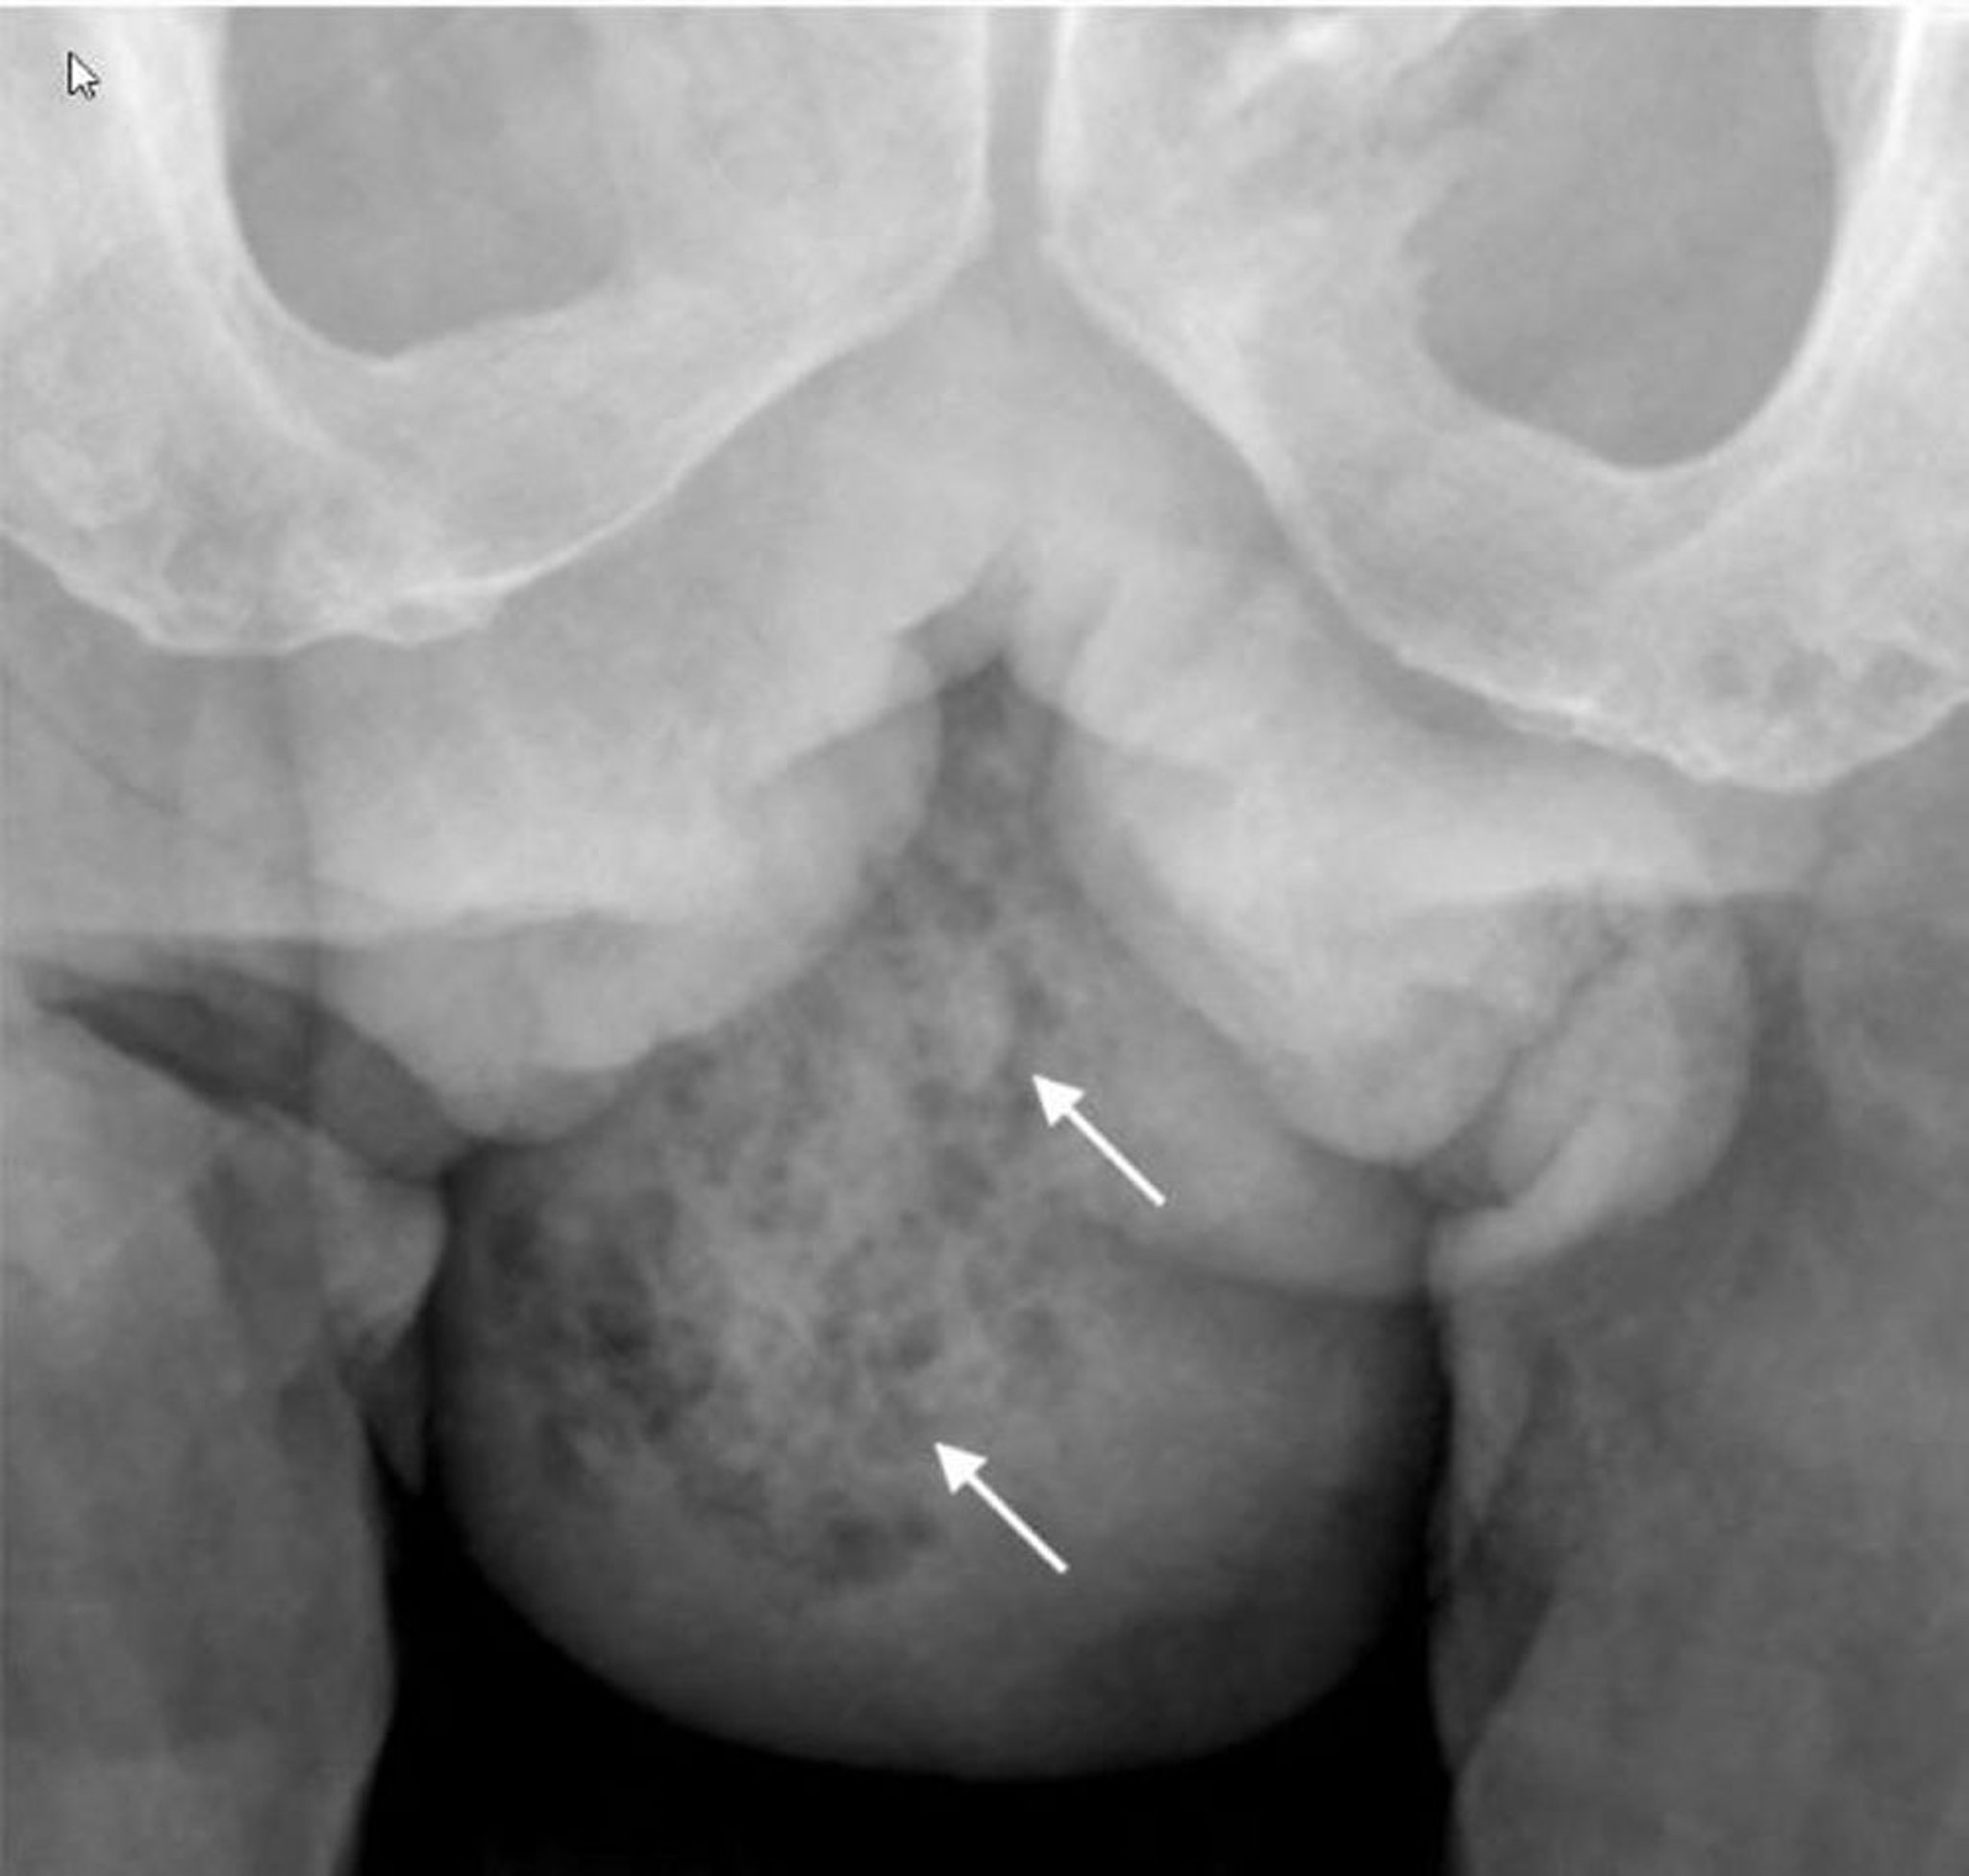

Cette radiographie montre un gaz dans les tissus mous de l'hémiscrotum droit (flèches).